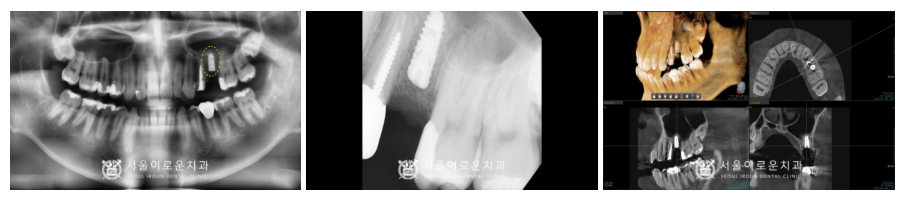

파노라마와 C T촬영을 통해

임플란트가 안정적으로

잘 식립 된 것을 확인하였으며,

식립 후 4개월 정도 충분한 시간을 가진 뒤

임플란트와 주변 치조골과의 결합이

단단히 되었는지 골 유착 정도를 확인하는

ossstell beacon이라는 장비를 이용하여

안정적인 것 확인하고

보철 과정을 진행하였습니다.

다른 보철 과정들도

환.자분의 식사나 불편함을 고려하여

순차적으로 진행해 드렸습니다.